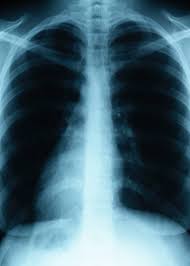

Cigarettes have many harmful chemicals that break down the lungs and can be leading causes in cancer. Asbestos exposure also exposes the lung to harmful chemicals that weaken your body’s defenses against cancers and other lung problems. Studies have found that cigarette smokers have a four to eleven times greater chance of getting lung cancer than non-smokers. If a person is a heavy smoker, than the number goes up to twenty-seven times as likely. Adding a heavy smoker to asbestos exposure sends the probabilities for lung cancer skyrocketing. In fact, heavy smokers with a history of asbestos exposure have a 50 to 90 times greater chance of having lung cancer. Needless to say, heavy smoking and large amounts of asbestos exposure will almost certainly lead to lung cancer.

Smoking causes chronic obstructive pulmonary disease (COPD). People who smoke and have been exposed to asbestos have higher occurrences of COPD than people who have not been exposed to asbestos. Some of the terrible effects of COPD are the inflammation and eventual destruction of small airways in the lung tissue. Once these tissues have been destroys, some people can be completely debilitated.